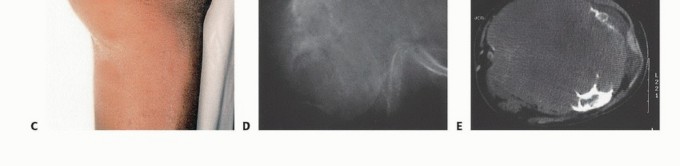

- الأشعة السينية (Plain Radiography): غالبًا ما توفر الأشعة السينية أول إشارة للحاجة إلى البتر وتقدير مبدئي لمستوى البتر المطلوب. يمكن أن تكون الصور العرضية لعظم الفخذ والساق مفيدة في إظهار انتشار الورم ومدى تدمير العظام. ومع ذلك، قد لا تظهر النتائج الإشعاعية إلا بعد تدمير ما يصل إلى 30% من بنية العظم.

- التصوير المقطعي المحوسب (CT) والتصوير بالرنين المغناطيسي (MRI): تعتبر هذه التقنيات الأكثر فائدة في تحديد مستوى انتشار الورم داخل النخاع العظمي ومدى انتشاره خارج العظم، وهو ما يستخدم لتحديد مستوى البتر. يُعد التصوير بالرنين المغناطيسي أيضًا مفيدًا لإظهار انتشار الورم في الهياكل العصبية الوعائية، مما يستدعي البتر غالبًا. كما أنه الدراسة التصويرية الأكثر موثوقية في تحديد وجود النقائل القافزة (skip metastases)، والتي قد تغير مستوى البتر.

- فحص العظام (Bone Scan): مفيد في تحديد مدى انتشار الورم داخل العظم؛ وتتوافق نتائجه جيدًا مع التصوير بالرنين المغناطيسي.